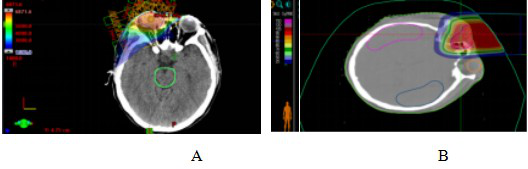

病例2:男性,38岁,右眼脉络膜恶性黑色素瘤。于2023年4月就诊于我院,眼底检查见视盘界清色淡红,网膜颞下象限可见一棕黑色高隆起性肿物,肿物周边继发性视网膜脱离,波及黄斑区。经过对患者全面检查和评估,患者于2023年4月25日至5月12日接受CIRT治疗。处方剂量为:PTV 70Gy/14Fx,5GyE/Fx。仰卧位,2D均匀扫描技术,剂量分布见图4。CIRT和VMAT计划在均满足处方要求的前提下,在轴位图像剂量分布的典型对比,周围正常组织CIRT计划较VMAT计划低剂量照射范围明显缩小,见图5。治疗期间给予患者特瑞普利单抗注射液(240毫克)免疫治疗2周期。CIRT治疗前、后通过影像学资料对比疗效,根据RECIST1.1肿瘤疗效评价标准评估患者疗效,治疗后3个月疗效为CR,见图6。CIRT治疗期间及治疗后1月内,患者出现1级放射性皮肤损伤,视力同前,未观察到大于2级的不良反应,治疗后3个月视力改善。截至2024年9月,目前患者无病状态,继续长期随访。

图4 脉络膜恶性黑色素瘤患者CIRT治疗剂量分布图

Figure 4 CIRT dose distribution in patients with malignant choroidal melanoma

图5脉络膜恶性黑色素瘤患者VMAT计划及碳离子计划剂量分布图

Figure 5 VMAT plan and carbon ion plan dose distribution in patients with malignant choroidal melanoma

Note: Figure 5A: VMAT plan dose distribution in patients with malignant choroidal melanoma. Figure 5B: Carbon ion plan dose distribution in patients with malignant choroidal melanoma.